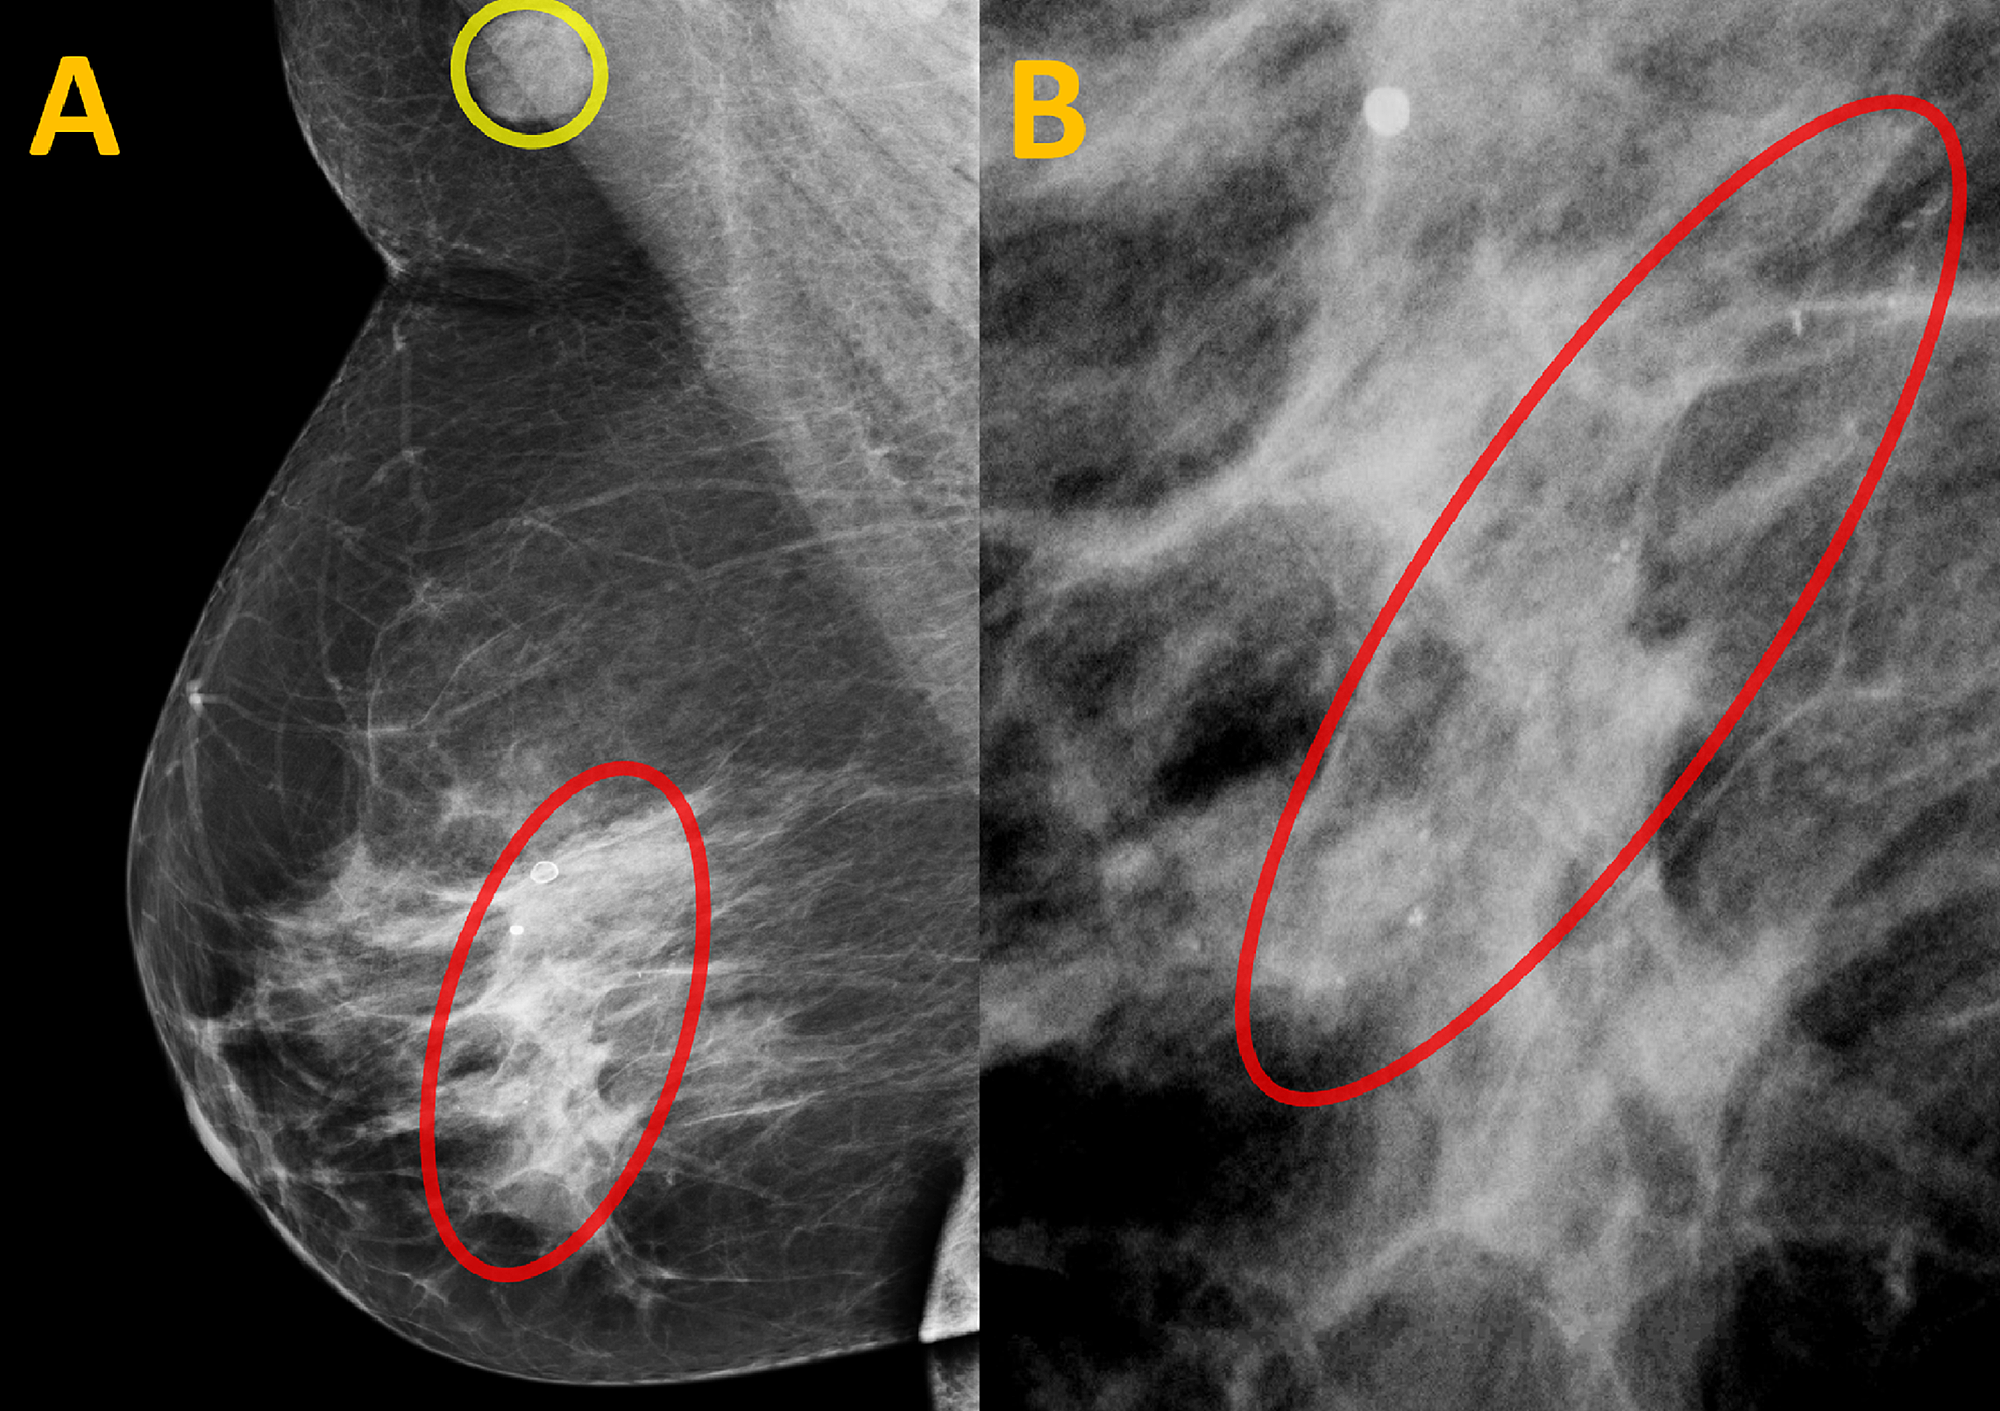

There’s a change from the last mammogram.

They appear as white spots or flecks on a mammogram but can't be felt during a breast exam. A new group has formed. For women treated for breast cancer in the past, calcifications may also be due.

There are numerous causes for calcium deposits in the breasts, including: But, japanese food natto has the ability to decalcify and maintain uniform level of calcium throughout the body and parts. Breast calcifications. california pacific medical center: